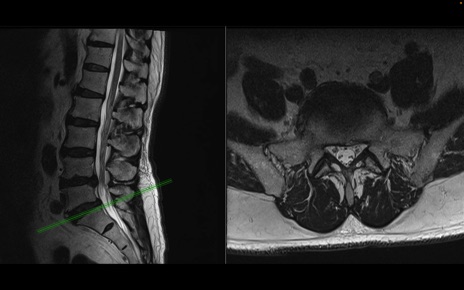

【整形】TIPS症例2 腰椎MRI 横断像と矢状断像

【症例】70歳代男性

【主訴】左下肢痛

【現病歴】2週間前くらいから腰痛、左下肢痛あり。左臀部から大腿、下腿外側のしびれが常時ある。歩行とともに同部位の痛みあり。

【身体所見】Lasegue70-/60+、Bragard-/±、PTR ±/±、ATR -/-、IP 5/5、TA 5/4、TS 5/5、EHL 右第1足趾なし/3、FHL 5/5、hypersthesia(-)、足背動脈触知良好

異常所見と診断は?